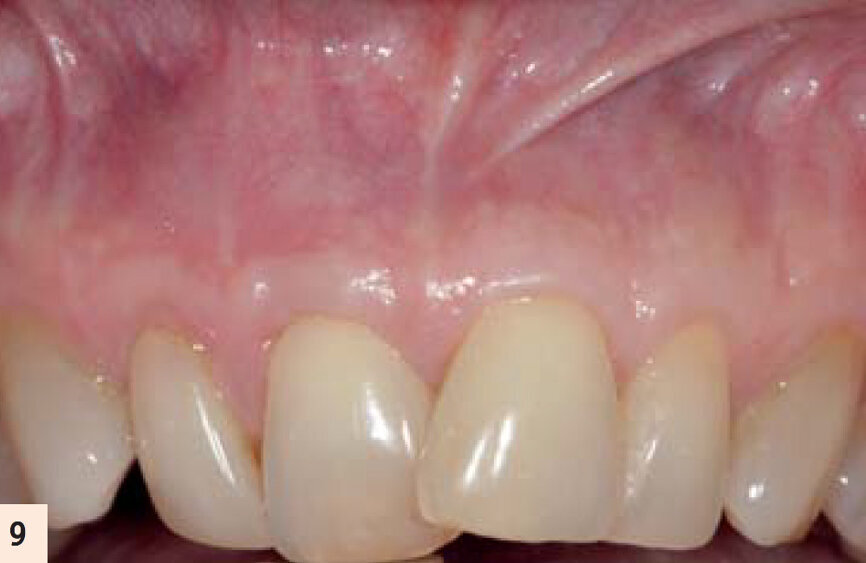

figure 9 : Deux ans postop. Noter le recouvrement radiculaire complet et l’augmentation de la zone de tissu attaché et kératinisé.

figure 10 : Vues pré- et postop (2 ans). Noter l’augmentation tridimensionnelle de la zone de tissu kératinisé et attaché, ayant pour résultat la restauration de la perte d’attachement et la correction de la

déformation gingivale en hauteur et en largueur.